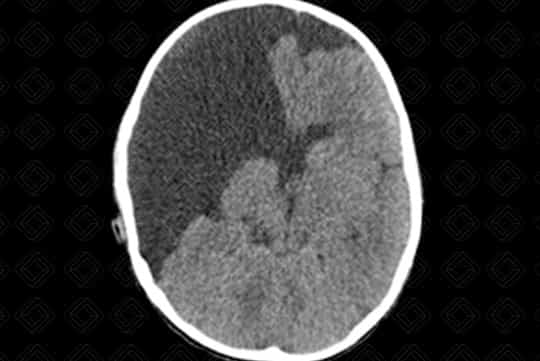

Descrição da lesão: Tomografia computadorizada do crânio com reformatações nos planos coronal e axial. Fenda preenchida por densidade liquórica na região parietal direita, caracterizando esquizencefalia de "lábios abertos" (primeira imagem).

Esquizencefalia : Trata-se de fenda transcortical delimitada por substância cinzenta. Elas podem ser de lábio aberto (grande defeito) ou lábio fechado (pequeno defeito). Até metade das esquizencefalias são bilaterais. Quando bilaterais, até cerca de 60% das esquizencefalias são de "lábios abertos" de ambos os lados.